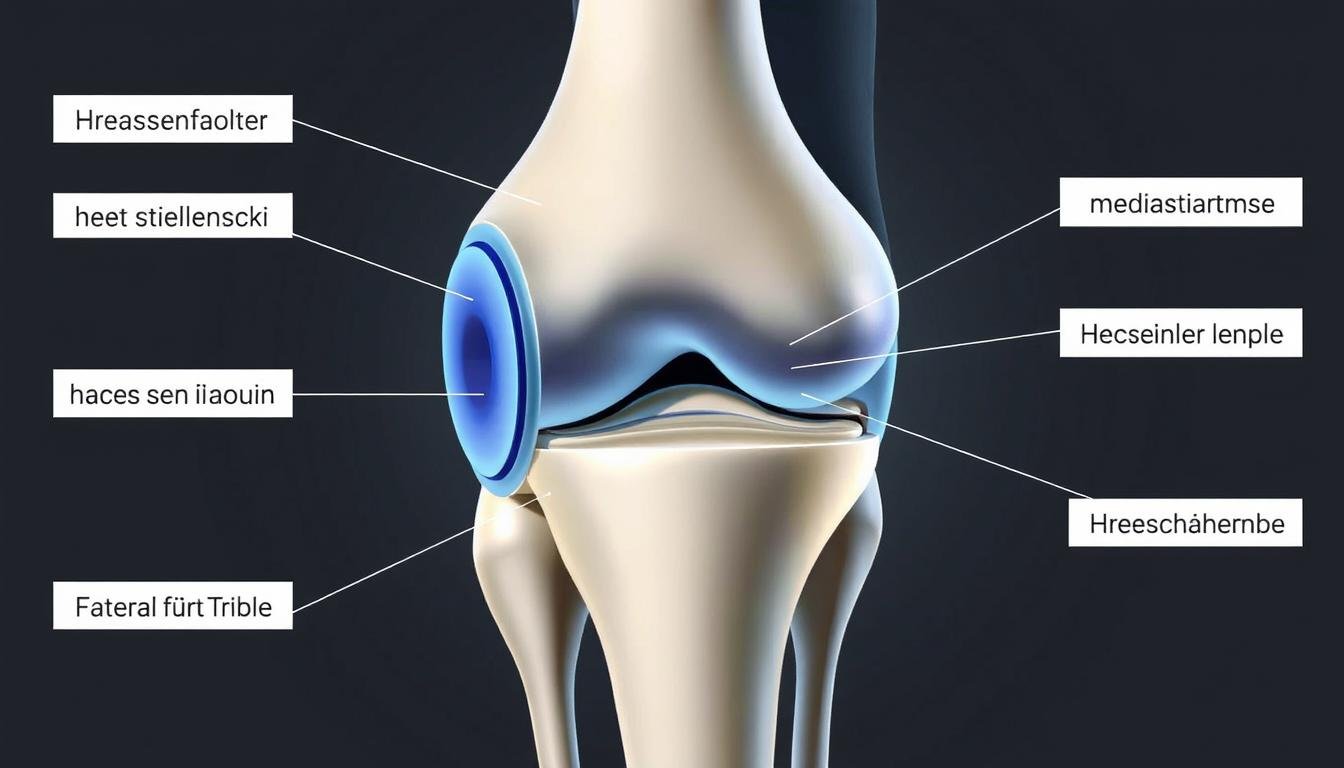

Anatomie des Meniskus im Kniegelenk mit Darstellung des Innen- und Außenmeniskus

Anatomie und Funktion des Meniskus im Kniegelenk

Der Innen- und Außenmeniskus im Kniegelenk dienen als Stoßdämpfer und Stabilisatoren zwischen Oberschenkel- und Unterschenkelknochen.

Das Kniegelenk verfügt über zwei halbmondförmige Menisken: den Innenmeniskus (medialer Meniskus) und den Außenmeniskus (lateraler Meniskus). Diese faserknorpeligen Strukturen erfüllen mehrere wichtige Funktionen: